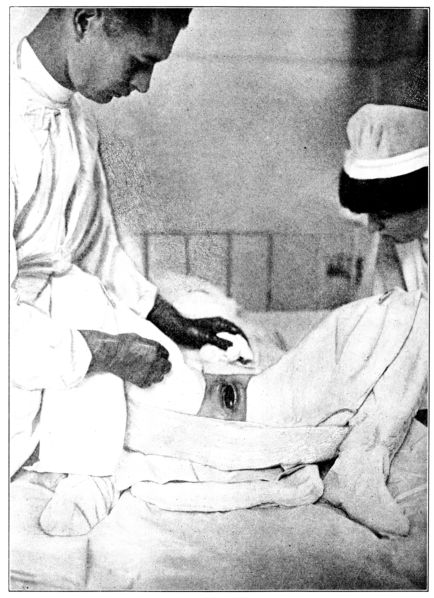

| 103. | Giving chloroform for obstetrical anæsthesia | 287 |

| 104, 105. | Giving ether for obstetrical anæsthesia | 289, 290 |